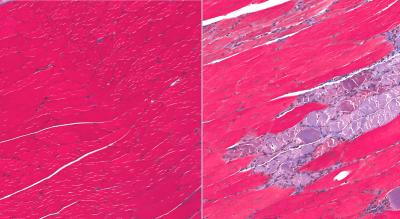

The research team first used normally aged mice and mice models of a form of muscular dystrophy that resembles the human disease to see what would happen if they were given a drug to inhibit STAT3. They found that the inhibitor initially promoted satellite-cell replication, followed by differentiation of the satellite cells into muscle fibers. When they injected the STAT3 inhibitor every seven days for 28 days, they found an overall improvement in skeletal-muscle repair, and an increase in the size of muscle fibers.